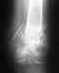

Закрытый перелом хирургической шейки левой плечевой кости со смещением. Выполнена закрытая ручная репозиция.

После 6 недель гипса доктор сообщил об образовании ложного сустава. Бабушке 75 лет. Подскажите есть ли возможность избежать в дальнейшем болей и улучшить работоспособность руки.

Похоже на несращение. Хотя для уточнения надо и посмотреть пацинтку, и сделать снимки в других проекциях. Если нет сращения, и есть болезненные проявления - лучше сделать остеосинтез. Можно обратиться в институт травматологии, к нам в отделение (Московская, 12) с 9 до 14 в рабочие дни. Паспорт, полис и снимки захватите.